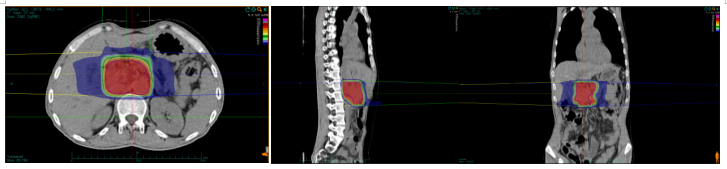

因胰腺病灶压迫十二指肠水平部导致高位消化道肠梗阻,引起胃潴留及进食后呕吐,患者入院后行营养管置管及胃肠减压,保证营养支持充足及胃排空状态前提下,于2020-12-29日开始碳离子治疗,剂量:55.2Gy(RBE),共治疗12次。治疗第7次疼痛明显缓解,治疗期间肿瘤标志物明显下降。治疗后一个月患者完全正常饮食,肿瘤缩小,治疗6个月后肿瘤坏死,活性完全消失。

胰腺癌碳离子治疗靶区计划

碳离子治疗后胰腺癌疗效评价